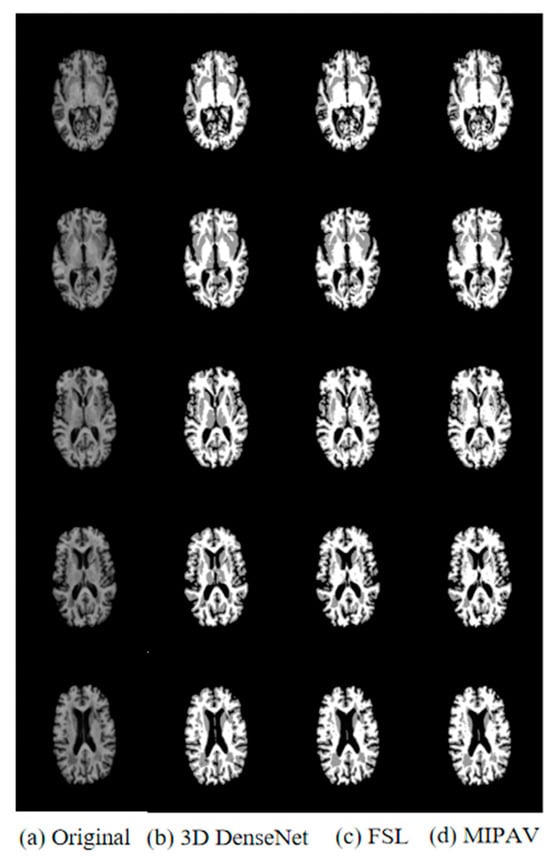

Figure 7 shows four sequential slices of the brain MR images of the subject’s sample data after segmentation by different segmentation methods. In the figure, the first column is the four slice graphs of the original T1-weighted image, the fifth column is the truth value image manually segmented by experts, and the second, third, and fourth columns are the results of the sample segmentation by applying the improved 3D DenseNet segmentation algorithm, MIPAV, and FSL, respectively.

Figure 8 compares the results of the segmentation of data obtained from ADNI datasets based on different methods. The first column shows five sequences of the original T1-weighted image, and the second column shows five sequences of the proposed improved 3D DenseNet segmentation model. The third and fourth columns show the results of segmentation using FSL and MIPAV traditional automatic segmentation software, respectively. As can be seen from the figure, the segmentation method proposed in this paper is relatively more complete, clearer, and more accurate in the segmentation of images in ADNI datasets, and the segmentation effect is better than that of using medical software tools. The application of the 3D DenseNet segmentation model to AD diagnosis can improve the performance of the algorithm more effectively. Therefore, the improved 3D DenseNet segmentation model is used to segment the obtained classification data before AD classification.